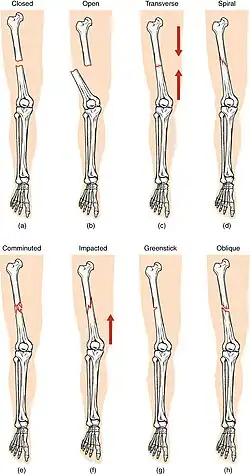

Compare healthy bone with different types of fractures:

(a) closed fracture

(b) open fracture

(c) transverse fracture

(d) spiral fracture

(e) comminuted fracture

(f) impacted fracture

(g) greenstick fracture

(h) oblique fracture